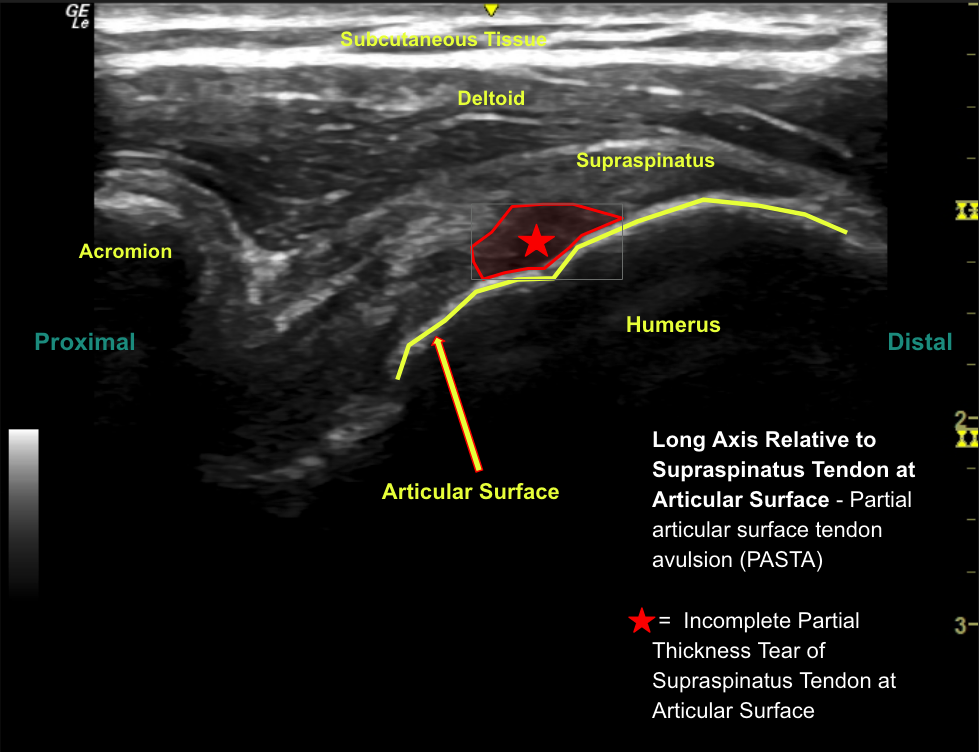

Labeled long axis view of the posterior supraspinatus at the articular surface with increased thickness of the tendon (approximately 4.9 mm) and no discrete tears.

Labeled long axis view of the anterior supraspinatus tendon at the articular surface with a small anechoic defect at the insertion consistent with a partial-thickness partial-width articular sided supraspinatus tendon tear.